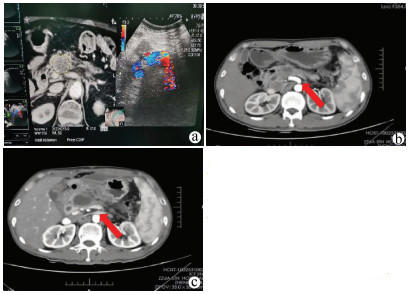

Effectiveness and safety of nanoknife ablation guided by real-time virtual sonography in treatment of locally advanced pancreatic cancer

•   Objective  To investigate the effectiveness and safety of nanoknife ablation guided by real-time virtual sonography (RVS) in the treatment of locally advanced pancreatic cancer (LAPC).  Methods  A retrospective analysis was performed for the clinical data of 27 patients with LAPC who attended The Fifth Affiliated Hospital of Zhengzhou University from April 2018 to October 2019, and according to the treatment method, the patients were divided into combination group (12 patients treated with IRE combined with chemotherapy) and control group (15 patients treated with chemotherapy alone). The chemotherapy regimen was gemcitabine combined with tegafur, gimeracil and oteracil potassium for both groups. Adverse reactions and complications were observed for the combination group during the perioperative period, and the two groups were compared in terms of the changes in myocardial enzymes, blood amylase, and carbohydrate antigen 19-9 (CA19-9) before treatment and at different time points after treatment, as well as remission rate (RR) and disease control rate (DCR) at 3 months after treatment and survival status during follow-up. The Mann-Whitney U test was used for comparison of non-normally distributed continuous data between groups, and the Wilcoxon test was used for comparison within each group; the Fisher's exact test was used for comparison of categorical data between groups; the Kaplan-Meier method was used to analyze the survival status during follow-up.  Results  In the combination group, there were 12 cases of adverse reactions and mild complications during the perioperative period, i.e., 9 Clavien-Dindo grade Ⅰ cases and 3 grade Ⅱ cases. All patients in the combination group experienced a transient increase in myocardial enzymes, which returned to normal within 7 days, and there were no significant changes in creatine kinase and lactate dehydrogenase on day 7 after treatment (P > 0.05); 9 patients had a significant increase in blood amylase on day 1 after surgery, which significantly decreased on day 7 after surgery and basically returned to normal on day 14 after surgery, and there was no significant change in blood amylase on days 7、14, and 1 month after surgery (P > 0.05). Before treatment, the level of CA19-9 was higher than the normal value in both groups, and the combination group had a significant reduction in CA19-9 at 1, 2, and 3 months after treatment (all P < 0.05); in the control group, the level of CA19-9 firstly decreased for a short time and then increased, while there was no significant change in CA19-9 at 1, 2, and 3 months after treatment (all P > 0.05). At 3 months after treatment, the combination group had significantly higher RR and DCR than the control group (RR: 75.0% vs 26.7%, P=0.021; DCR: 91.6% vs 53.3%, P=0.043). During the median follow-up time of 13 months, compared with the control group, the combination group had significantly higher median progression-free survival time (10 months vs 5 months, P=0.014) and median overall survival time (18 months vs 10 months, P=0.034).  Conclusion  RVS-guided percutaneous nanoknife ablation has marked clinical effect and high safety in the treatment of LAPC and can be used as a new treatment option for patients who refuse or cannot tolerate laparotomy for ablation therapy.